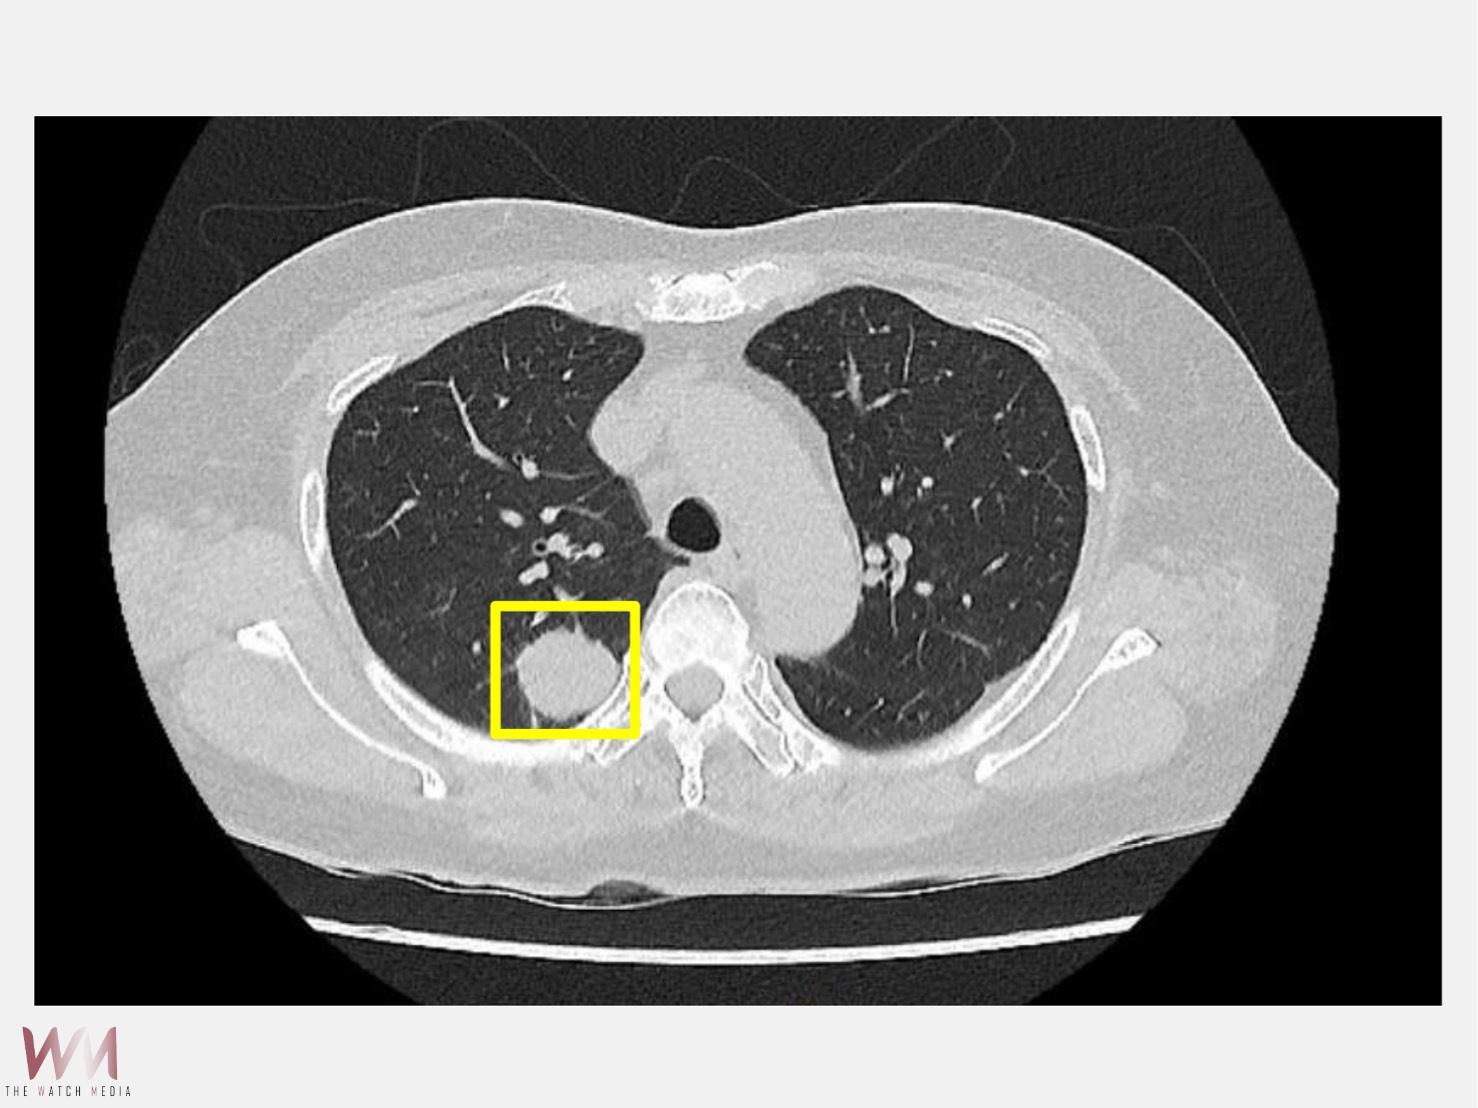

(觀傳媒中彰投新聞)【記者廖妙茜/台中報導】50歲的吳先生平時生活作息規律,從不抽菸,也沒有肺癌家族史,原以為自己身體健康的他在一次健康檢查中,經由低劑量電腦斷層(LDCT)意外發現右側肺部有一顆約2公分大小的腫瘤。吳先生前往仁愛長庚合作聯盟醫院(大里仁愛醫院)尋求醫療專業協助,經由胸腔暨心臟血管外科林宜右醫師詳細評估後,建議進行肺臟腫瘤切除手術,並且採用目前先進的「單孔達文西機器人微創手術」技術,在三天內順利出院。

林宜右醫師說,現代醫療的進步,是希望讓每一位病人都能以最小的負擔,獲得最完善的治療。並提醒,肺癌初期多無明顯症狀,凡是有吸菸史或家族病史的人,應定期接受低劑量電腦斷層篩檢(LDCT),及早發現及早治療,才能守護健康。